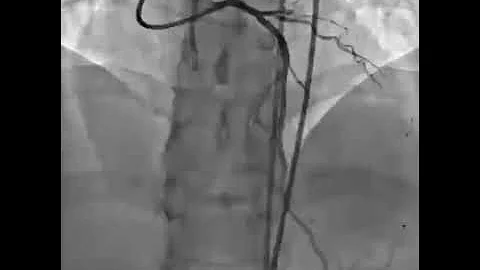

Cto Case : Reverse Cart Technique With Knuckling